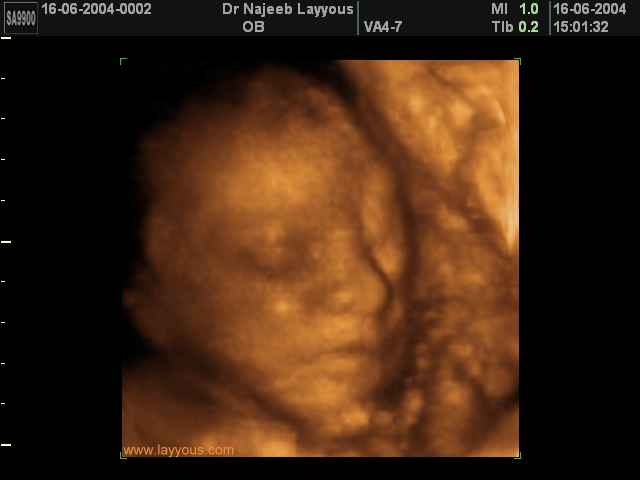

صور لوجه الجنين بجهاز الالتراساوند ثلاثي الأبعاد | الدكتور نجيب ليوس

صور لوجه الجنين بجهاز الموجات فوق صوتية ثلاثي الأبعاد